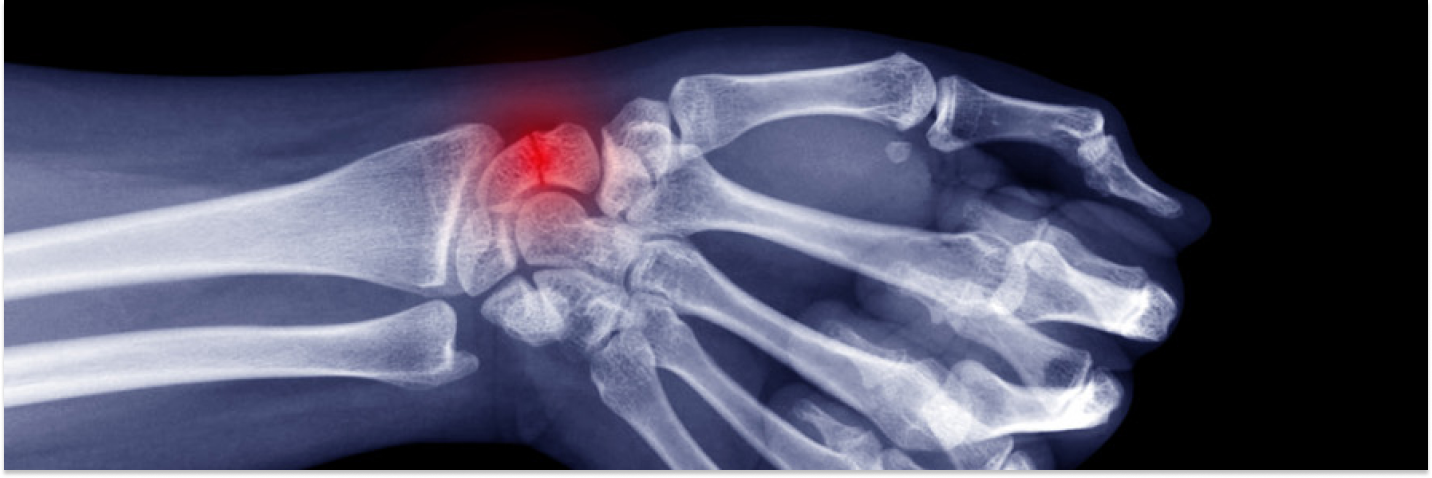

Scaphoid Fracture

A scaphoid fracture is a break in one of the small bones on the thumb side of your wrist. It can happen when you fall and catch yourself with your hand stretched out. It is important to get it checked, because this bone has a limited blood supply and doesn't always heal easily.